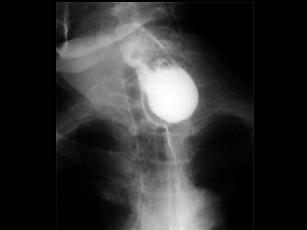

问题 男性患者,24岁,近2年来有胸骨后疼痛感,饮食睡眠情况可,体重不减轻,行X线钡餐检查,结果如图所示,最有可能的诊断是 ( )

选项 A、贲门失弛缓症 B、以上均不正确 C、食管平滑肌瘤 D、食管憩室 E、食管癌

答案 D